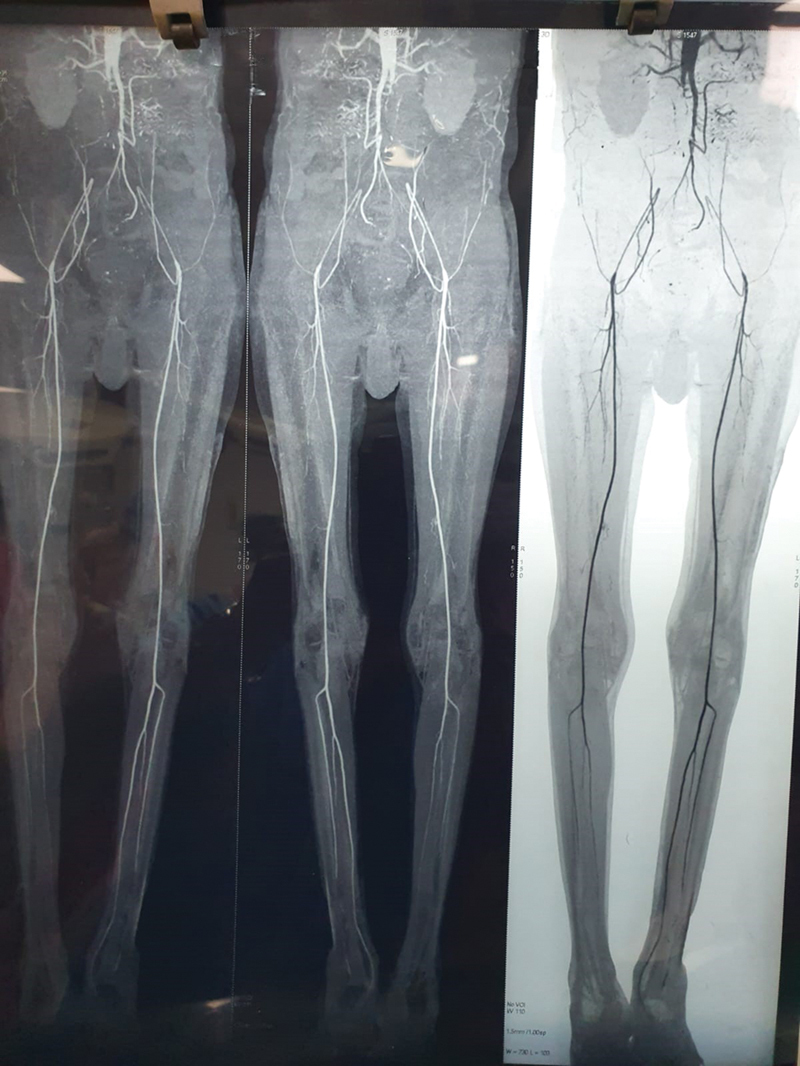

Thoracofemoral bypass is primarily utilized as a secondary intervention for juxtarenal aortoiliac occlusive disease, with limited instances of its application as an initial treatment, leading to uncertain long-term outcomes. This analysis aims to scrutinize the 10-year experience and early outcomes of 90 patients who underwent thoracofemoral bypass as a primary procedure.A retrospective analysis was conducted on patients undergoing thoracofemoral bypass for severe aortoiliac occlusive disease between August 2012 and August 2022. The primary indication was complete abdominal aorta obstruction at the renal artery level with an unsuitable site for aorta clamping. The BARD IMPRA expanded polytetrafluoroethylene vascular graft was employed for thoracobifemoral bypass surgery.Among the 90 patients, 83 (92.22%) were male, and 7 (7.78%) were female, with ages ranging from 51 to 77 years. Intraoperative and postoperative data were analyzed, and the mean follow-up duration was 30 days. The 30-day mortality rate was 3.33% (n = 3). Major morbidities included graft occlusion in one patient, managed by embolectomy, and ascites in another patient, addressed conservatively.This study demonstrates that thoracic aorta to femoral artery bypass, as a simple extra-anatomic bypass technique, can yield favorable outcomes when chosen as the initial treatment for patients with juxtarenal total aortoiliac occlusive disease. Thoracofemoral bypass exhibits a safe, acceptable outcome with reliable patency.

Abstract Image